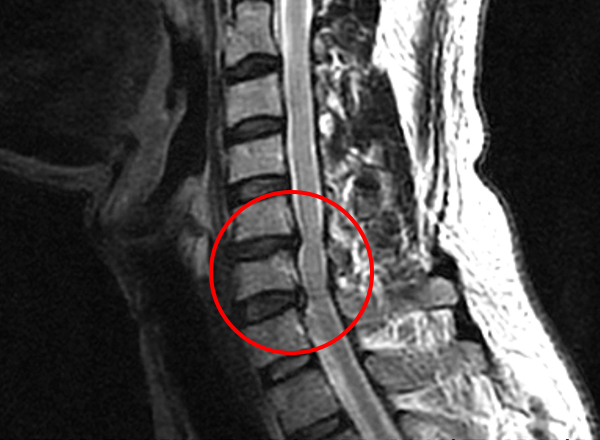

목디스크란 목뼈 사이에 있는 디스크가 손상되어 신경을 압박하는 질환을 의미합니다. 디스크는 젤리와 같은 수핵과 섬유륜으로 구성되어 있습니다. 섬유륜이 손상되면 수핵이 밖으로 밀려나와 신경을 압박하게 됩니다.

그래서 이러한 생활습관 등으로 인해 목디스크 발병률이 높아질 수 있습니다. 목디스크는 심할 경우 척추 협착증, 척추 손상, 신경 손상, 목뼈의 변형 및 골절 등의 심각한 질환으로 이어질 수 있기 때문에 사전에 미리 예방하는 것이 무엇보다 중요합니다.